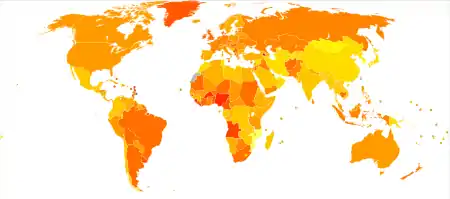

|

no data

<2

2–4

4–6

6–8

8–10

10–12 |

12–14

14–16

16–18

18–20

20–22

>22

|

Breast cancer is the most-common invasive cancer in women,[204] accounting for 30% of cancer cases in women.[205] Along with lung cancer, breast cancer is the most commonly diagnosed cancer, with 2.09 million cases each in 2018.[206] Breast cancer affects 1 in 7 (14%) of women worldwide.[207] (The most common form of cancer is non-invasive non-melanoma skin cancer; non-invasive cancers are generally easily cured, cause very few deaths, and are routinely excluded from cancer statistics.) In 2008, breast cancer caused 458,503 deaths worldwide (13.7% of cancer deaths in women and 6.0% of all cancer deaths for men and women together).[208] Lung cancer, the second most-common cause of cancer-related deaths in women, caused 12.8% of cancer deaths in women (18.2% of all cancer deaths for men and women together).[208]

The incidence of breast cancer varies greatly around the world: it is lowest in less-developed countries and greatest in the more-developed countries. In the twelve world regions, the annual age-standardized incidence rates per 100,000 women are as follows: 18 in Eastern Asia, 22 in South Central Asia and sub-Saharan Africa, 26 in South-Eastern Asia, 26, 28 in North Africa and Western Asia, 42 in South and Central America, 42, 49 in Eastern Europe, 56 in Southern Europe, 73 in Northern Europe, 74 in Oceania, 78 in Western Europe, and 90 in North America.[209] Metastatic breast cancer affects between 19% (United States) and 50% (parts of Africa) of women with breast cancer.[210]